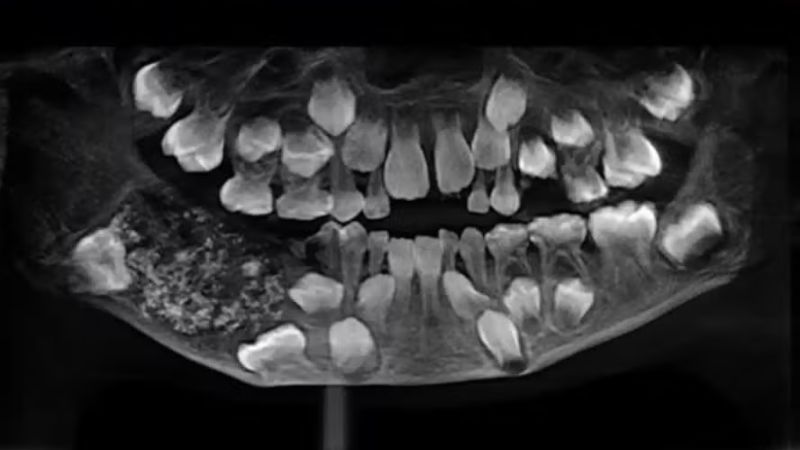

Após exames, foi identificado um odontoma composto com 526 dentes  |   Bnews - Divulgação Reprodução/Saveetha Dental College and Hospital

Natural da região de Tiruvallur, na Índia, a criança foi levada ao Saveetha Dental College and Hospital após apresentar inchaço e ausência de erupção dos dentes permanentes. Ao passar por exames de radiografia e tomografia, foi constatado uma uma massa de cerca de 200 gramas, identificada como odontoma composto, um crescimento benigno formado por tecido dentário irregular.

A cirurgia durou cerca de cinco horas e, em laboratório, os médicos encontraram os 526 mini-dentes, cada um com coroa, raiz e esmalte, variando de 0,1 mm a 15 mm. O caso do meno superou o recorde anterior de 232 dentes, registrado em Mumbai em 2014.